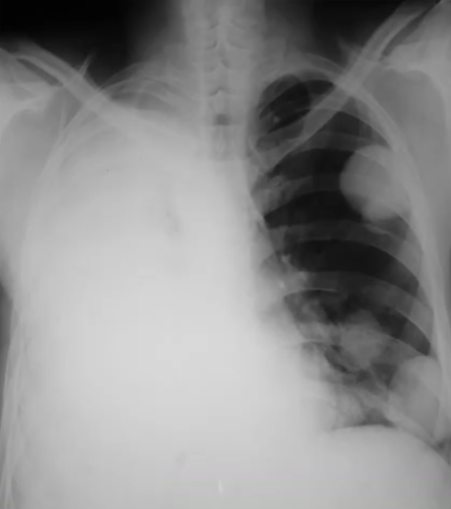

Rx toracică, incidență P-A

DESCRIERE:

la niv. întregului hemitorace stg → opacitate extinsă, nesistematizată, de intensitate mare, omogenă

caracter retractil → tracționează traheea și mediastinul de partea afectată

fără bronhogramă aerică

duce la micșorarea spațiilor intercostale

la niv. hemitoracelui controlateral → hipertransparență compensatorie

DX: atelectazie prin NBP central endobronșic (pe bronhia principală stg)

DD: pleurezie masivă → caracter expansiv